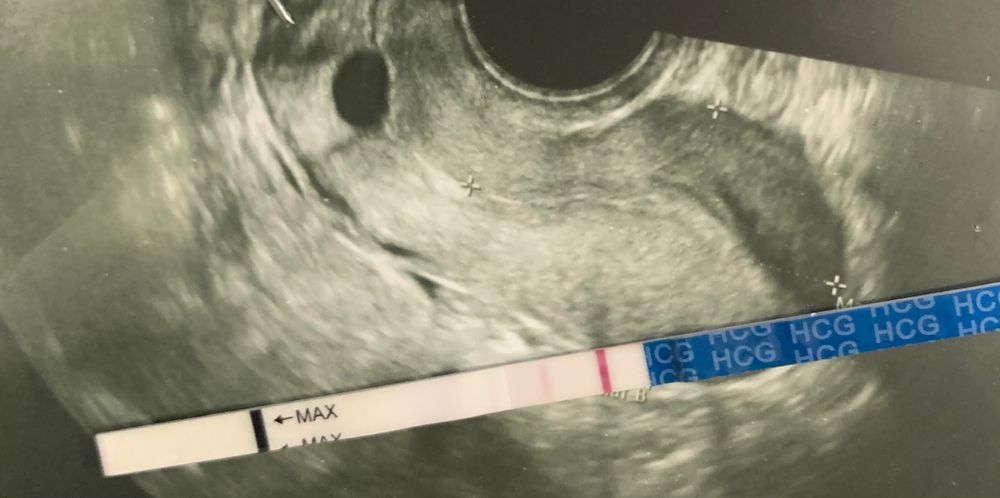

Здравствуйте. Возникли очень сильные боли внизу живота , поехала на узи , врач сказал беременности не видит, но увидел кисту. Приехала домой после узи, сделала ЭВИ ТЕСТ, вот такой результат выдал , а второй тест отрицательный… ничего не понимаю помогите разобраться , на узи плодной яйцо? Или эвик выдал такой реагент?

Надо сдать кровь на хгч если он меньше 1000 у вас на УЗИ ни чего не увидят.

Юлия, согласна. Хгч прояснит есть ли вообще Б, и киста ли это на снимке или уже плодное яйцо.

У меня эвик в прошлом цикле нарисовал точно такую же полоску. Через пару часов переделала фрау-чисто...))) надеюсь, что у вас то самое. У меня были кисты и в яичниках и киста желтого тела, но тест ни разу 2 полосы на них не выдавал. Мы не врачи здесь, и ориентироваться на мнение бб не стоит. Поддержать, порадоваться, погрустить с вами-всегда пожалуйста, но рекомендации, советы и пр-лучше с врачом.

Я не врач, но вообще мое ранее узи так же примерно и выглядело, и киста была желтого тела или как-то так это называется. Что б не переживать сходите хгч сдайте, можно даже доплатить и вам результат в течении 4 часов придёт. Хгч точно не обманет

Плодного яйца при таком тесте быть не может видно. Если у вас есть беременность, то это покажет кровь на хгч

А эвитесты мне вот прям такой реагент недавно и выдал, так что я им не верю больше

Тест у вас положительный. Просто срок ещё маленький, поэтому на узи не видно

С таким тестом на узи ещё беременности не будет видно, так что скорее всего киста дала такой результат

У моей знакомой была похожая ситуация. Она делала тесты эви, он выдавал такие полоски, уже радовались. Сходила на узи, сказали киста и чуть позже пришли месячные.

Много раз слышала, что если есть киста то тест будет слабоположительный